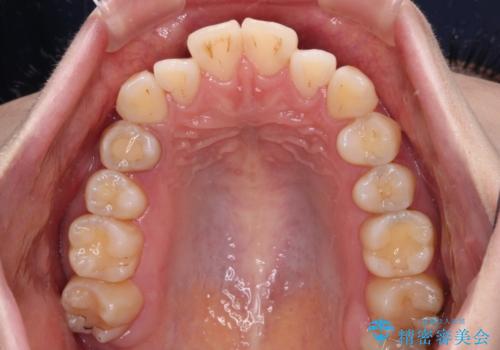

舌突出癖による開咬 舌のトレーニングを行いながら前歯の隙間を改善

- 上下前歯の隙間を気にして来院された患者様です。

前歯が、舌の突出癖により上下前歯が非接触となっている状態でした。

ワイヤー矯正での開咬改善には時間がかかります。

舌の突出癖改善のトレーニングをしっかりと行っていただき、上下前歯が接触する咬み合わせを達成することができました。